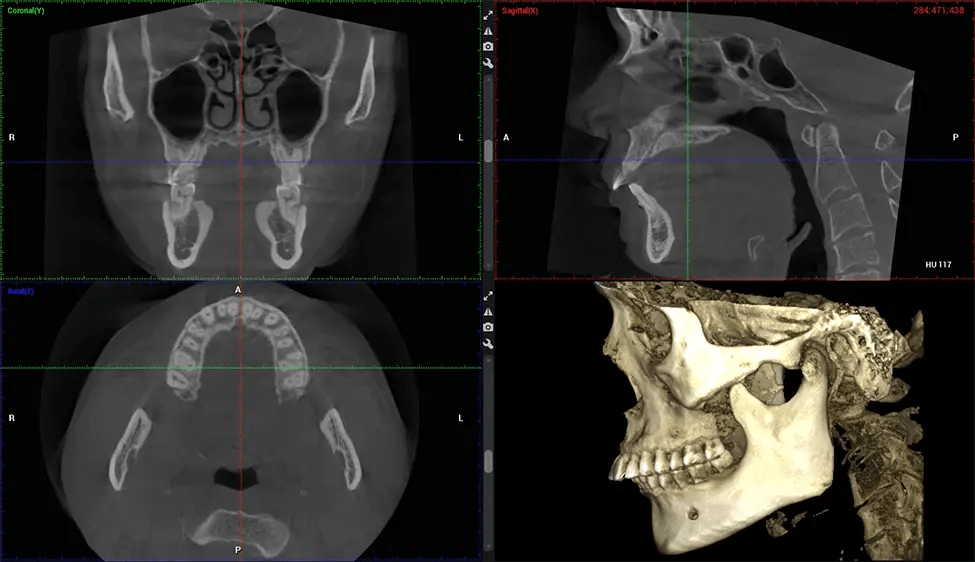

Cone Beam Computed Tomography (CBCT) is an advanced imaging technique used in dentistry and maxillofacial surgery to obtain detailed 3D images of the oral and maxillofacial structures. At Dr G Dental Studio, our CBCT scanners utilize a cone-shaped X-ray beam and a specialized detector to capture images from different angles. A computer then combines these images to create a 3D representation of the patient’s oral anatomy.

After the scanning process, the captured X-ray images are processed by the CBCT software, which applies algorithms to reconstruct a detailed 3D image of the scanned area. The software compiles these individual X-ray images and creates a digital 3D representation of the patient’s anatomy. The reconstructed 3D CBCT image can be viewed and analyzed by the dentist or radiologist. This image can be manipulated, rotated, and zoomed in or out to examine specific structures and evaluate the patient’s condition.